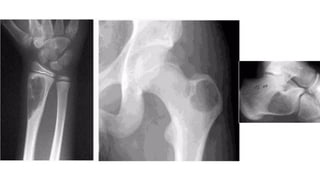

• • Lower limb = 75% ( metaphysis)

• • Calcaneum>femur >tibia>fibula

• • Upper limb

• • Skull and mandible

• • Spine & pelvis

• • Ribs

Plain radiograph feature

• Expansile radiolucent lesion with sharply defined

• sclerotic margin

• • No periosteal new bone formation

• Within calcaneum, lipoma has characteristic

• appearance, osteolytic lesion with a central focus

• o f o s s i fi c a t i o n

• CT & MRI

• • Can be homogenous fat content

• • Fatty lesion with central necroses, central

• calcifications o r o s s i fi c a t i o n s

• • Fatty lesion with multiple central necroses, central

• calcifications or ossifications

Differentials for intraosseous lipoma - SBC and Bone infarct